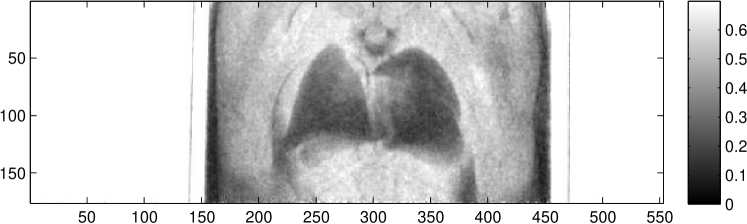

In situ lung imaging of two healthy C57BL/6 adult mice was performed to obtain information on the signals of phase-contrast imaging. Figure 3 shows the three images obtained of the lungs of a mouse in posterior-anterior (p.a.) orientation, using eight phase steps with and an acquisition time of each at a tube current of . This corresponds to an air kerma of measured at the object position with a calibrated IBA Dosimax plus A HV dosimeter with the solid-state detector unit RQX 70kV.

While the lung tissue is only weakly visible in the absorption image in Figure 3 the bony structure of the mouse thorax can clearly be seen. In the differential-phase image the fur of the animal is clearly visible. Both lungs as well as the spinal cord of the animal are shown. The speckle noise in the phase image described by Kitchen et al. (2004) can be observed in the expected lung area. Dark field imaging highlights clearly the fur-air interface as well as both lungs with their typical anatomical structures and sizes. Furthermore, the boundaries of the chest wall are clearly visible in the dark field and the differential-phase image.

First of all, three images containing different tissue properties are gained with one imaging process. This leads to an increase in information from which radiologists can make a more profound diagnosis. An example for the complementarity of information in the three images is shown in Figure 3. There, the absorption image is dominated by the bones of the animal and is therefore a good source for information about the skeletal structure and its diseases, like bone fractures. In the differential-phase image on the other hand, the bones are suppressed. Furthermore, the soft tissue contrast and the tissue edges are enhanced. This leads to a high organ visibility as in the differential-phase image of Figure 3 the lungs and the upper airways can be seen. The third image quantity, the dark field is a measure of the granularity of structures. Because of this, the lung, which consists of many alveoli, produces a high dark field signal.